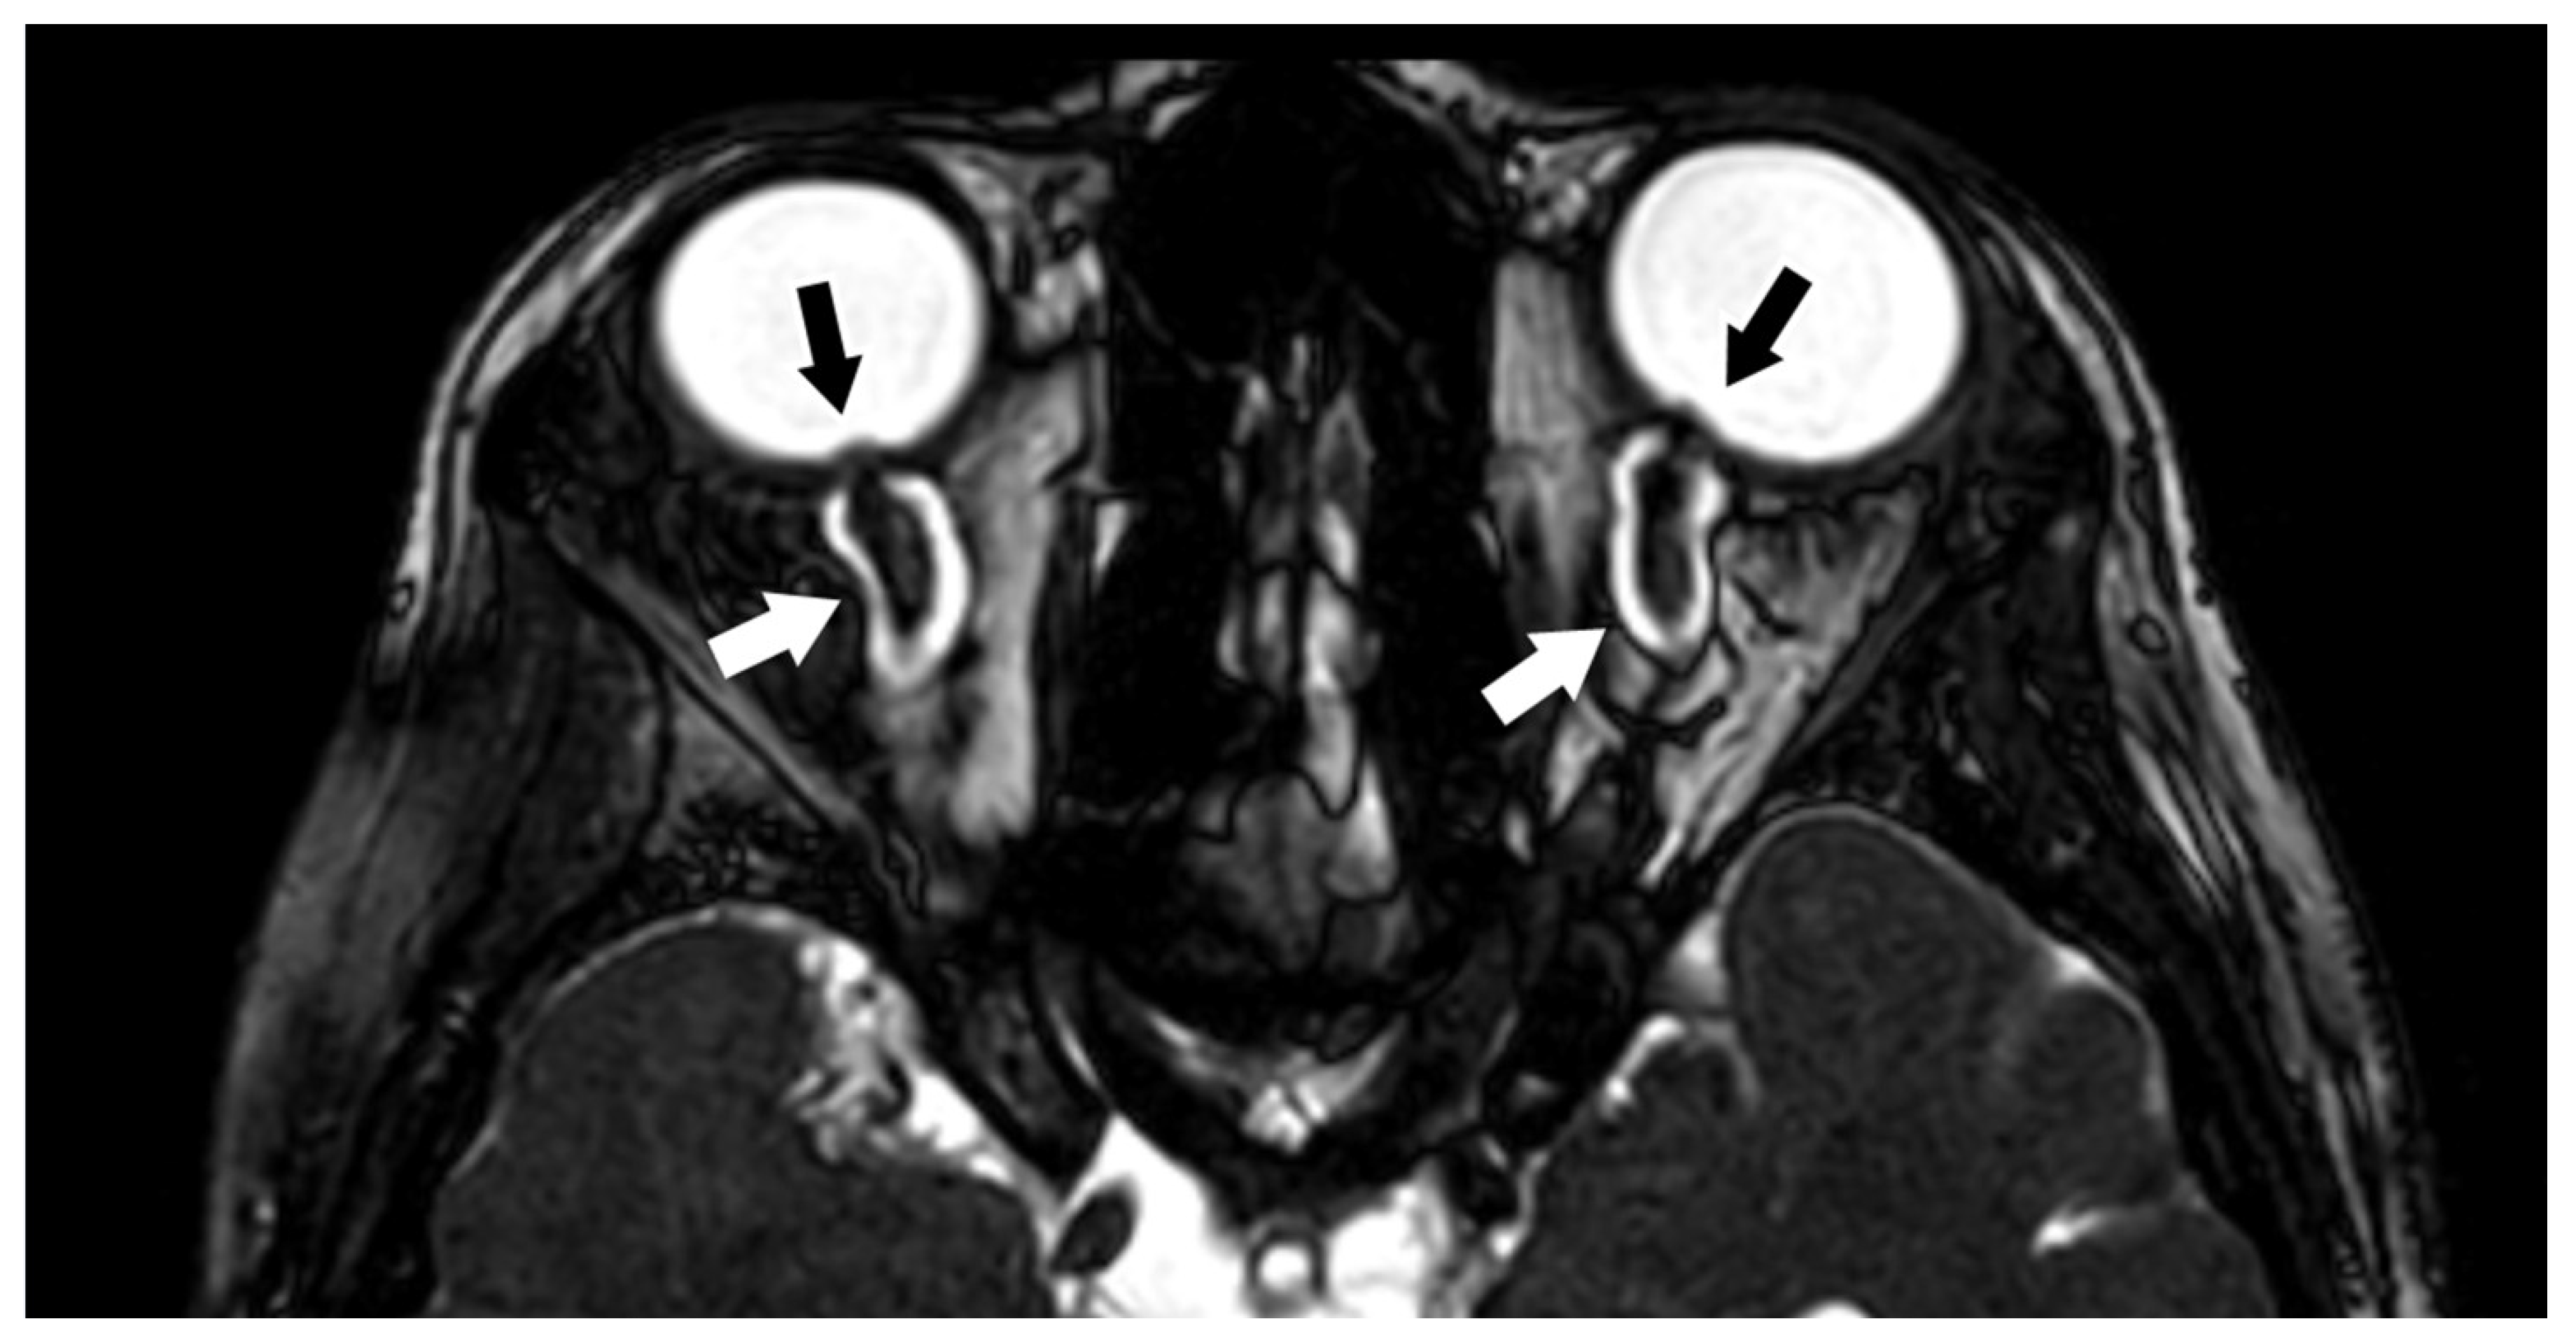

3.1.2. Optic Nerve (II) and Orbital Masses

3.12. Neonatal and Fetal MRI